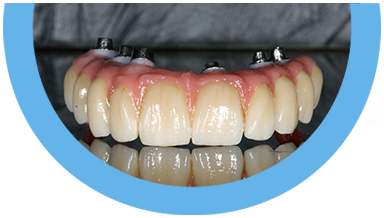

Paciente de 76 anos do sexo masculino

Motivo da consulta: Paciente desdentado total, procurava colocar dentes.

Plano de tratamento: Colocação de 4 implantes superiores e 2 implantes inferiores. Confeção de uma barra superior e colocação de 2 locators® na parte inferior. Confeção de uma prótese superior e outra inferior removível, com encaixes na barra e locators®.

A escolha deste plano de tratamento deve-se ao facto de o paciente querer uma solução total, mas não completamente fixa, uma vez que não tinha muita destreza manual para higienizar uma prótese fixa. Desta forma, conseguiu uma solução bastante retentiva (devido aos encaixes) mas que consegue remover para uma higienização correta.